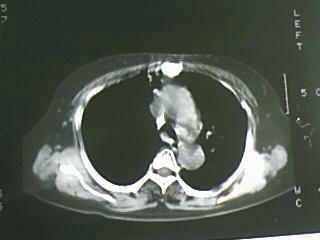

以下是引用bmw011在2009-4-14 19:14:00的发言:[br]右肺继发型肺结核---纵隔淋巴结多发钙化----左肺支扩。支持

以下是引用杀毒软件在2009-4-14 17:52:00的发言:[br]考虑---右肺继发型肺结核---纵隔淋巴结多发钙化----左肺支扩

以下是引用黑白光影在2009-4-14 20:36:00的发言:[br]右肺继发型肺结核;左下慢性支气管炎性病变。